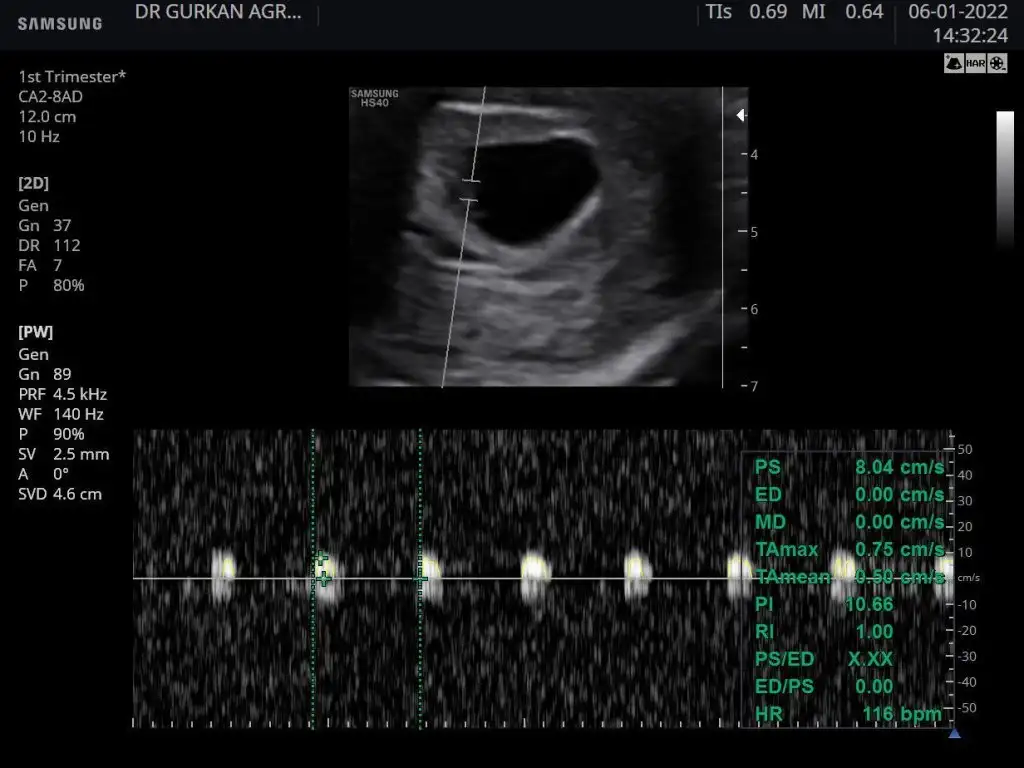

Kızlar bu bebiş doğdu eski usg si bu karından çekildi sizce kızmı erkek mi. Bakalım ramzi tutuacakmı

Eklentiler

• 0DCEF50D-ACE6-4185-8097-6F4BE314F73F.webp

41,6 KB · Görüntüleme: 74

• F171D4CC-1C2D-471D-8781-B2D9429E59F7.webp

21,8 KB · Görüntüleme: 79

• 14C4C8ED-DA59-4461-A23B-D4F4C45BBCF8.webp

22,9 KB · Görüntüleme: 70